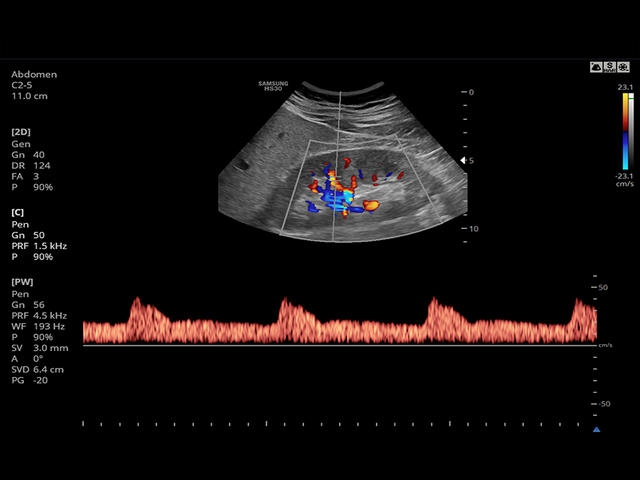

Сосуды брюшной полости: автоматическая, полуавтоматическая, ручная трассировка доплеровского спектра; ПСС, КДС, %СтПлощ, %Ст Диам, площадь сосуда, диаметр сосуда, объемный кровоток.

- PW - импульсно-волновой допплер, steering - изменение допплеровского угла в режимах CD и PD, автоматический анализ допплеровских кривых.